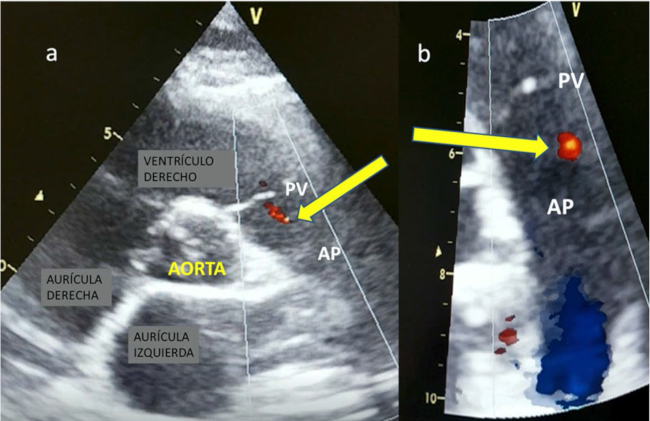

Se trata el caso de un paciente varón de 18 años, jugador de rugby profesional, sin antecedentes y con un VO2 máximo de 61 ml/kg/min. Presentó un examen físico normal y un electrocardiograma sin alteraciones patológicas. En el ecocardiograma Doppler, sobre el plano eje corto grandes vasos, se identificó mínimo flujo Doppler color sobre la pared del tronco de la arteria pulmonar (AP) a 4-5 mm del plano valvular (PV), que no parecía corresponder a un reflujo valvular pulmonar (Figura 1a y 1b, flecha).